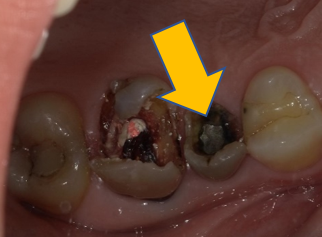

| 0114 #16 右上第一大臼齒 |

![]() |